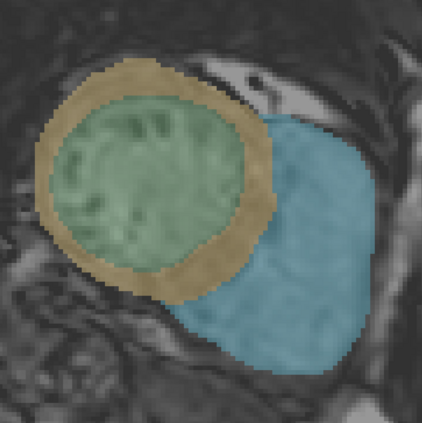

In cardiac magnetic resonance (CMR) imaging, a 3D high-resolution segmentation of the heart is essential for detailed description of its anatomical structures. However, due to the limit of acquisition duration and respiratory/cardiac motion, stacks of multi-slice 2D images are acquired in clinical routine. The segmentation of these images provides a low-resolution representation of cardiac anatomy, which may contain artefacts caused by motion. Here we propose a novel latent optimisation framework that jointly performs motion correction and super resolution for cardiac image segmentations. Given a low-resolution segmentation as input, the framework accounts for inter-slice motion in cardiac MR imaging and super-resolves the input into a high-resolution segmentation consistent with input. A multi-view loss is incorporated to leverage information from both short-axis view and long-axis view of cardiac imaging. To solve the inverse problem, iterative optimisation is performed in a latent space, which ensures the anatomical plausibility. This alleviates the need of paired low-resolution and high-resolution images for supervised learning. Experiments on two cardiac MR datasets show that the proposed framework achieves high performance, comparable to state-of-the-art super-resolution approaches and with better cross-domain generalisability and anatomical plausibility.